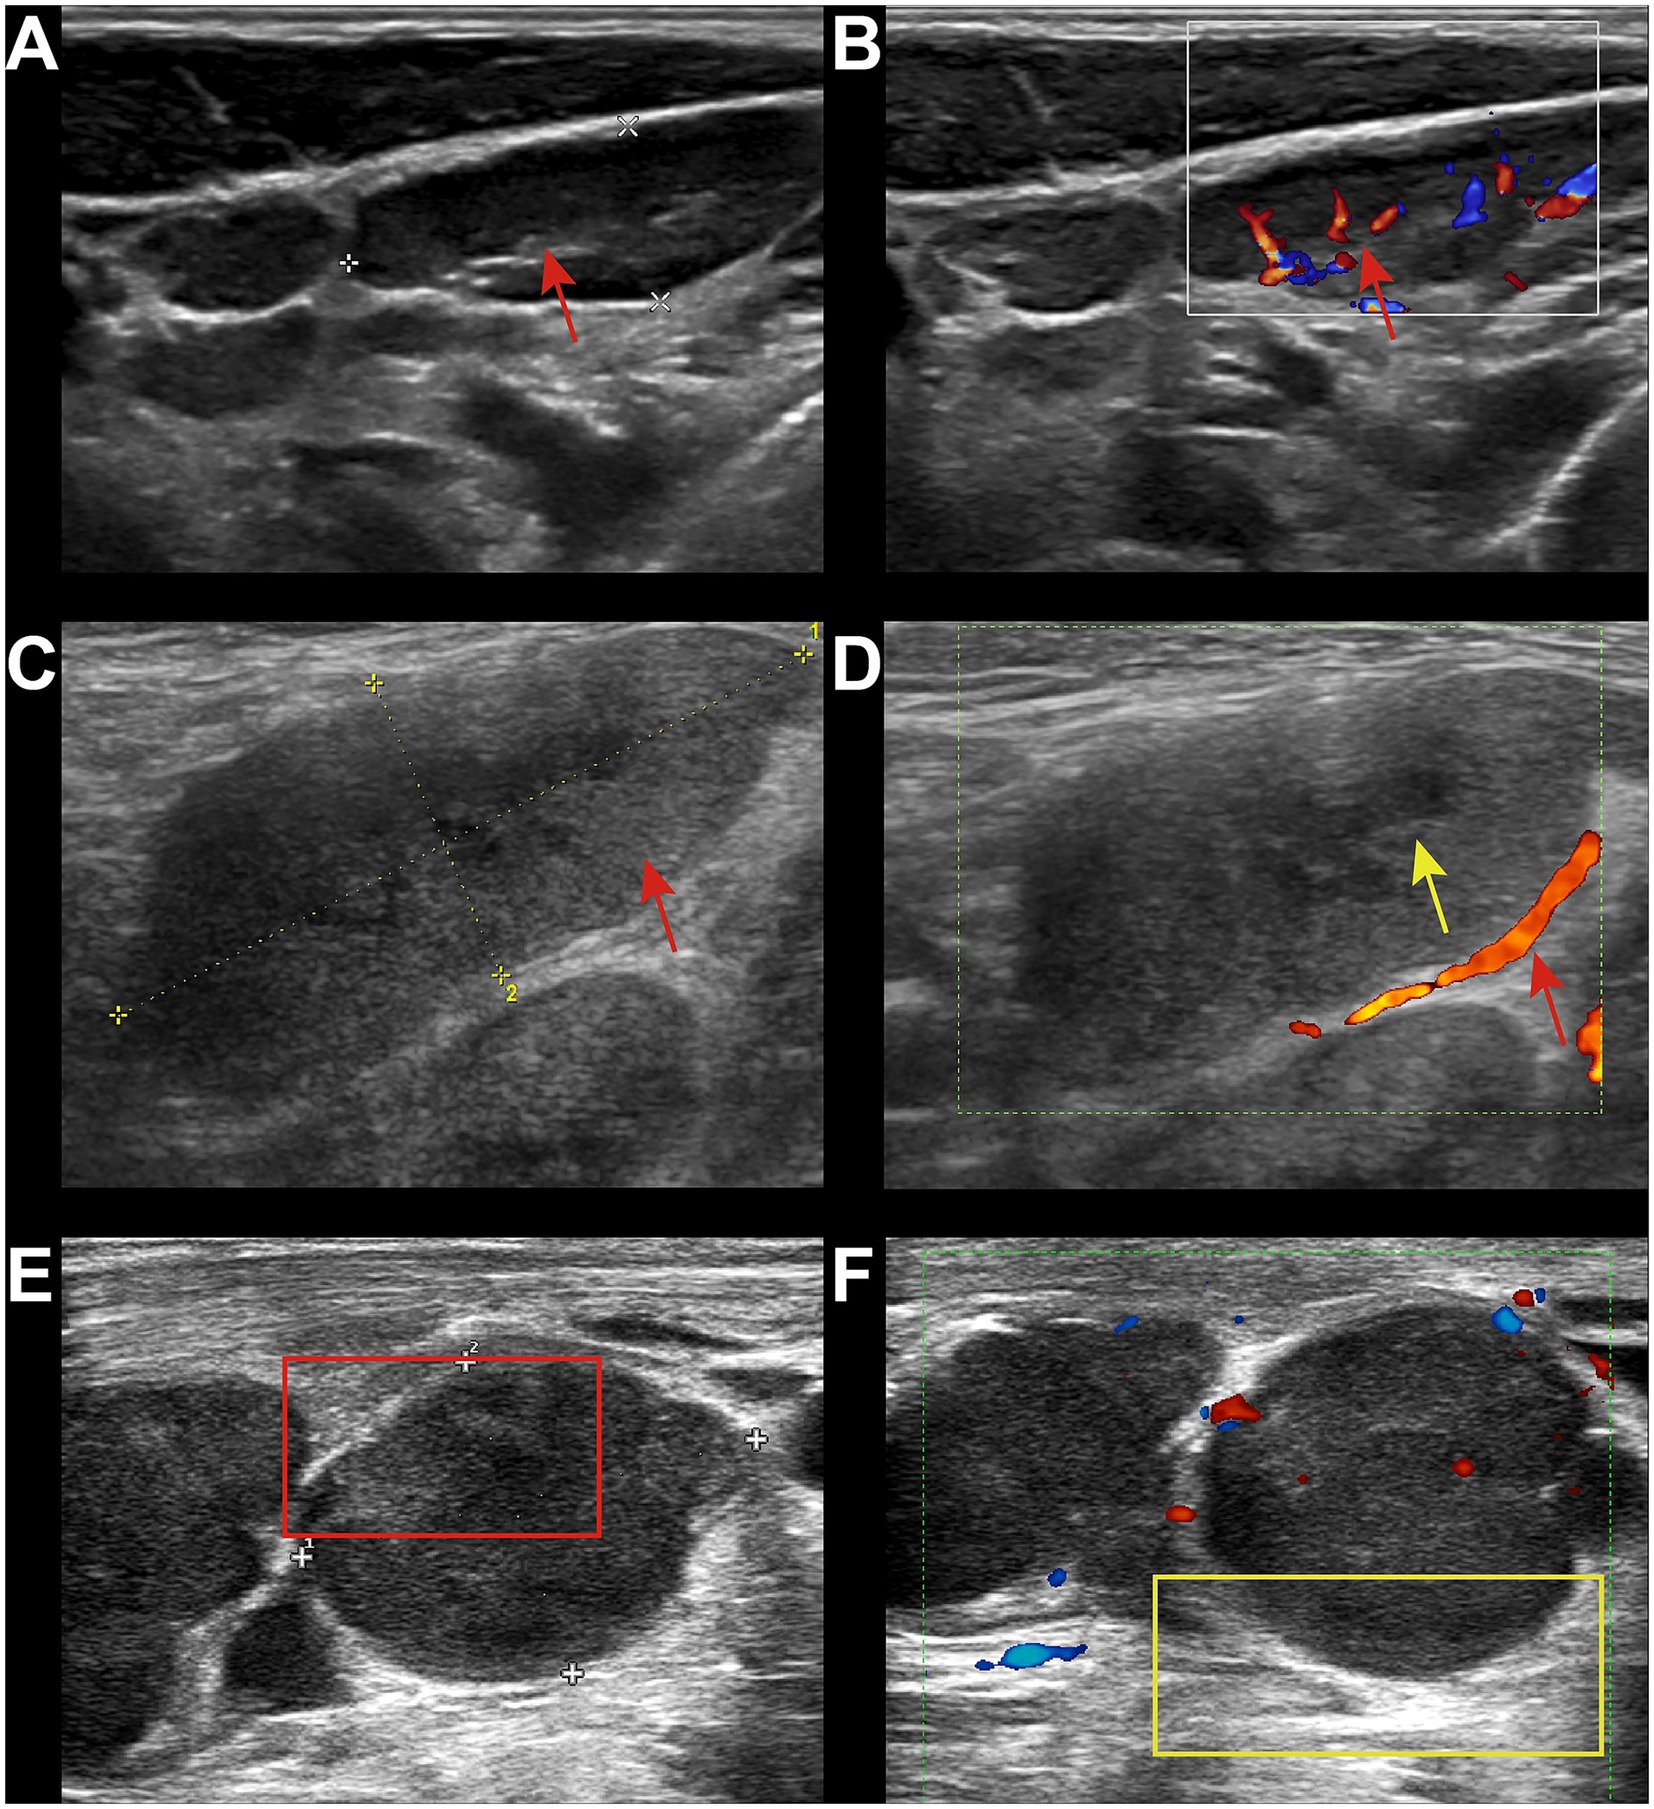

Reactive lymphadenopathy was commonly characterized by regular lymph node shape, clear margins, and the presence of a lymph node hilum, with abundant blood flow signals demonstrated on Color Doppler Flow Imaging (CDFI) (Figures 1A,B). Tuberculous lymphadenopathy varied in presentation depending on the disease stage. In the early stage, it resembled reactive lymphadenopathy. In the middle and late stages, lymph nodes fused with each other, resulting in irregular shapes and ulceration, forming sinus tracts (Figures 1C,D). Cystic changes were relatively common within the lymph nodes, and internal calcifications and surrounding soft tissue edema may be observed. Fungal infections typically presented with regular lymph node shape and mostly uniform increased echogenicity within the lymph nodes (Figures 1E,F). A few cases may showed cystic changes. The lymph node hilum was often absent or thinned. Blood flow patterns on CDFI were variable, with no significant edema in the surrounding tissues and no calcifications observed. Lymphoma involvement of lymph nodes usually manifested as round or oval lymph nodes with a full appearance, which fused (Figures 2A,B). When fused, the lymph nodes were often large, sometimes exceeding 10 cm, and the shape was usually irregular. The lymph node hilum was frequently absent. With low gain settings, the lymph node may appear anechoic, while increasing the gain reveals a reticular echogenic pattern within the lymph node. Metastatic lymph nodes were often multiple, with round or irregular shapes and an L/S ratio <2 (Figures 2C,D). The margins were clear, but may appeared blurred if the lymph node capsule was invaded. The lymph node hilum may be thinned, compressed eccentrically, or even completely absent. The cortex was irregularly thickened, and the internal echogenicity was heterogeneous.

Figure 1. Ultrasound images of benign group. (A) 24-year-old male, diagnosed with HIV infection for 4 years. Left cervical lymph node showed enlargement with regular shape, clear margins, and visible lymph node hilum (red arrow). (B) CDFI showed abundant hilar blood flow (red arrow). The pathological diagnosis was reactive lymphoid hyperplasia. (C) 36-year-old male, diagnosed with HIV infection for 6 years. Multiple lymph node enlargements in the right axilla with regular shape had increased internal echogenicity (red arrow). (D) A few cystic changes were visible (yellow arrow), with the absence of the lymph node hilum. CDFI showed minimal peripheral blood flow (red arrow). The pathological diagnosis was fungal infection, with the final culture result identifying Talaromyces marneffei infection. (E) 48-year-old male, diagnosed with HIV infection for 8 months. Multiple lymph node enlargements were in the right neck with regular shape and heterogeneous internal echogenicity (red box). (F) The lymph node hilum was absent, and surrounding soft tissue edema was present (yellow box). CDFI showed minimal peripheral blood flow signals. The pathological diagnosis was TB.